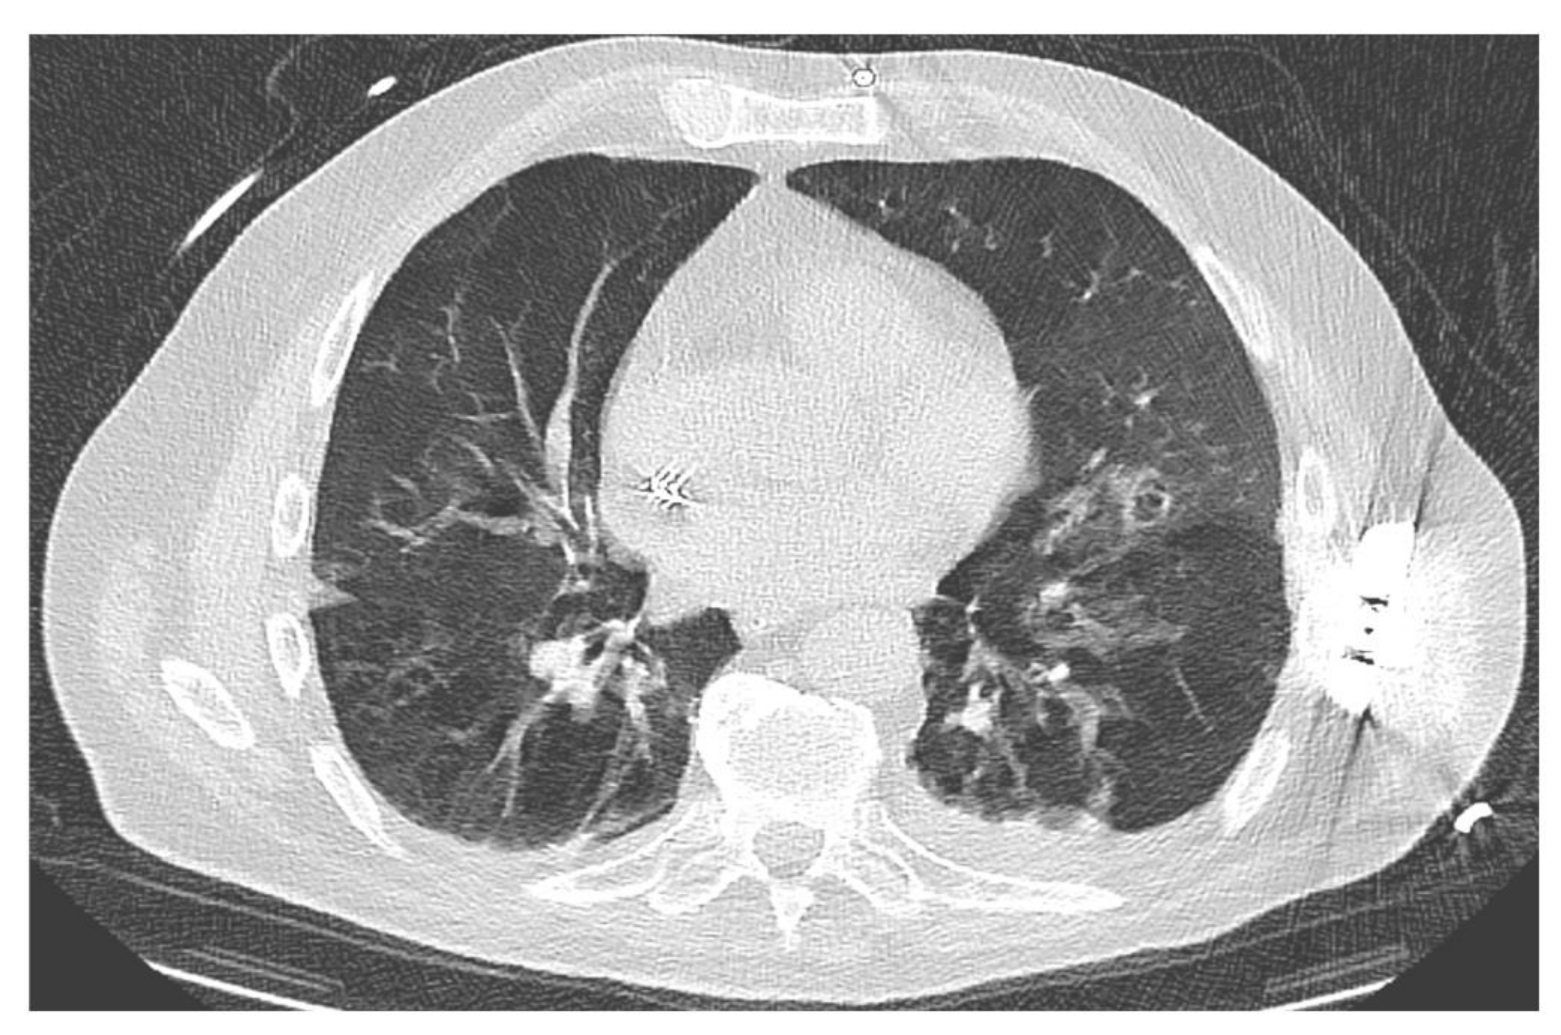

3.6. Fungal Infection and Antifungal Treatment

3.8. Case Reports: